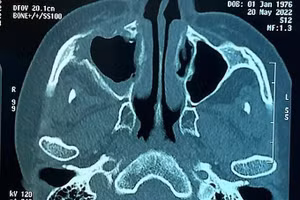

GD&TĐ - Thời gian gần đây, một số bệnh viện tại Thành phố Hồ Chí Minh đã tiếp nhận nhiều bệnh nhân bị hoại tử xương hàm bất thường, trong đó có một số ca tử vong, các bệnh nhân đều có điểm chung là từng mắc Covid-19.

GD&TĐ - Cục Quản lý khám, chữa bệnh (Bộ Y tế) đã có văn bản đề nghị các bệnh viện có thông tin chính xác dựa trên cơ sở khoa học về các ca bệnh bị hoại tử xương hàm mặt liên quan đến hậu Covid-19, tránh làm hoang mang bất ổn trong xã hội.

GD&TĐ - Thông tin từ Bệnh viện Chợ Rẫy (Thành phố Hồ Chí Minh) cho biết, đã tiếp nhận hàng loạt bệnh nhân bị hoại tử vùng xương sọ, mặt sau khi mắc Covid-19 gây nguy hiểm tính mạng, thậm chí có trường hợp đã tử vong.